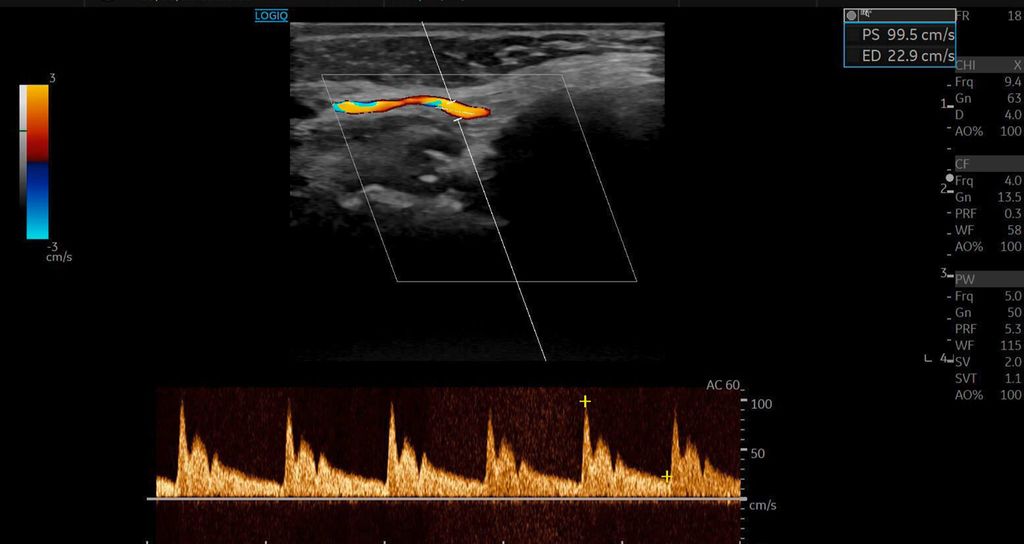

Die Duplexsonografie ergab folgende Befunde (Abb. 5 und Abb. 6):

Der Durchmesser der A. angularis und A. facialis hatte sich nahezu verdoppelt.

Die systolische Spitzengeschwindigkeit (PSV) stieg von 20cm/s auf über 100cm/s.

Die enddiastolische Geschwindigkeit (EDV) betrug nun 20cm/s, was auf eine periphere Vasodilatation und eine Wiederherstellung der Makrozirkulation hindeutete (Abb. 7).